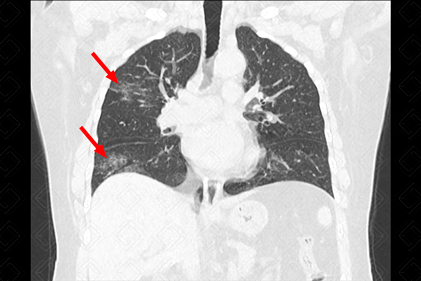

Descrição das figuras 4, 5, 6 e 7: Radiografia e nova tomografia de tórax, realizadas 4 dias após admissão, evidenciando piora dos achados pulmonares. Importante aumento das opacidades em vidro fosco periféricas.

• Opacidades em vidro fosco, bilaterais, acometendo a maioria dos lobos pulmonares (acometimento multilobar), assimétricas e com predomínio na periferia dos pulmões;

• Em associação às áreas em vidro fosco, pode coexistir o espessamento dos septos interlobulares, caracterizando o padrão de pavimentação em mosaico;

• Diante da evolução desfavorável, pode ocorrer aumento das opacidades em vidro fosco, com surgimento de áreas de consolidação;